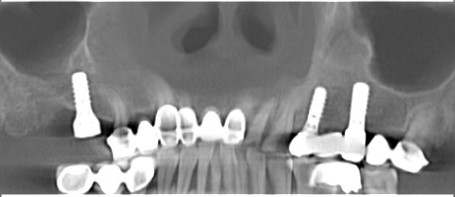

数字化种植导板:让种植牙更精准、更安全、更微创

近年来,科技迅猛发展,随着计算机辅助软件在口腔诊疗领域的拓展应用,基于口腔CBCT扫描数据的3D打印数字化种植导板在口腔种植外科手术中被广泛运用。这种相较于传统依靠医生临床经验的新型数字化种植路径,大大改变了患者的就医体验。利用数字化导板引导口腔种植外科手术,在很大程度上实现了更精准、更安全、也更微创。同时,也在很大程度上拉近了医患之间的沟通与交流,让医患双方在术前就能获得一定的手术预期性。

数字化种植导板是通过导板设计软件对CBCT、口扫等一系列数据的系统性分析,辅助口腔种植位点的设计,然后通过3D打印技术等途径进行导板生产,从而实现精准定位的种植手术装置。

简单来讲,数字化种植外科导板(简称导板),是将术前软件设计的种植方案,精确转移至患者口内的个性化手术辅助配件。

在数字化种植导板下的外科手术更加精准。种植体植入方向、位置、角度、深度等一目了然,即可将种植体精准植入到最佳位置,获得更优异的临床效果,手术安全性更高。